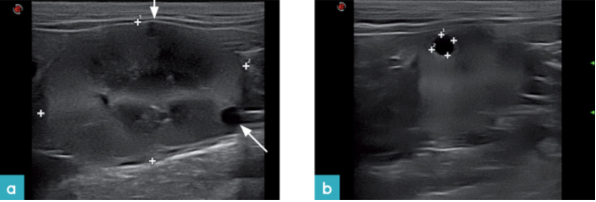

囊肿表现为圆形的无回声或低回声腔,通常位于肾皮质或髓质中,与实质能很好的区别开来,并具有薄壁(图18.视频9)。随着年龄增加直到最终囊肿甚至可以完全替代正常肾实质并引起肾损伤,而且囊肿的数量和大小变化很大。囊肿往往是中空的,但其中一些可能含有血液,或者可能存在低回声或内部回声(图19.视频10)。